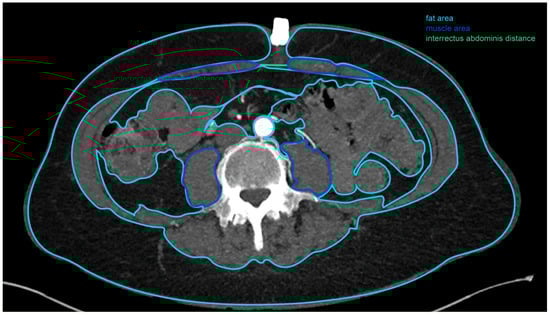

2.2. Computed Tomographic Angiogram Measurements